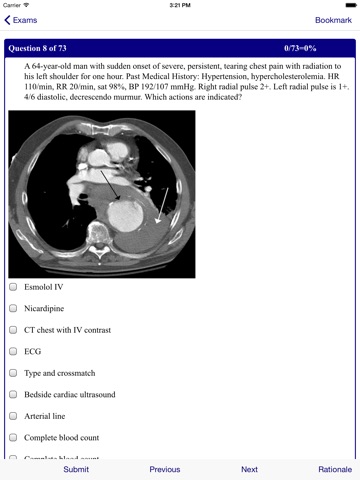

Emergency Medicine Review Emergency Medicine Review provides the full spectrum of emergency medicine at your fingertips on your iPhone device. Includes 300 Emergency Medicine Board clinical scenario review questions. NOW IN COLOR Written by clinicians engaged in the day-to-day practice of emergency medicine, this app is the most trusted app in emergency care. Composed of brief chapters focusing on clinical features, diagnosis, and emergency management, Emergency Medicine Review is designed to help you provide skillful and rapid patient care. This expanded and revised app is enhanced by: A full color design with photos and drawings Numerous tables, making information easy to access Completely revised and reorganized content to match current practice New chapters on Acute Coronary Syndromes, Thromboembolism, Occlusive Arterial Disease, Nausea and Vomiting, Trauma, and Bowel Obstruction and Volvulus. With its unmatched authority and easy-to-use organization, Emergency Medicine Review belongs in the pocket of every clinician working in acute medical care.

Poorly designed. Images associated with cases do not correspond. The rationale for management questions do not make sense; correct answer is not revealed. Complete waste of money.